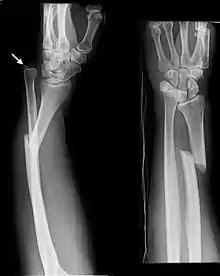

An ulna fracture is a break in the ulna bone, one of the two bones in the forearm.[2] It is often associated with a fracture of the other forearm bone, the radius.[1][3]

An ulna fracture can be a single break as in a so called nightstick fracture, which can be caused by someone being hit on the inside of the forearm often by a stick, notably when they are holding their arm up to protect their head from injury.[2][4] The ulna bone can also break after falling on the forearm or falling on an outstretched arm.[2]

Fractures of the ulna can occur at different levels of the bone: near the wrist, in the middle or near the elbow.[2] The fracture may be confined to the ulna or accompanied with damage to the radius or the wrist or elbow joints.[2]